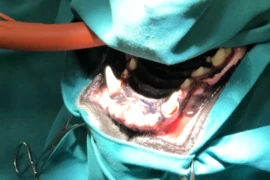

Robert Marx graduierte 2019 als Doktor der Veterinärmedizin (DVM) an der Veterinärmedizinischen Universität Budapest. Danach zog es ihn zurück nach Deutschland, um in der multidisziplinären Kleintierklinik Hofheim in Hessen zu arbeiten. Nach einer allgemeinen Rotation begann er seine spezialisierte Weiterbildung in allen Bereichen der routinemäßigen und fortgeschrittenen zahnärztlichen Versorgung unter der Leitung von Dr. Andrea Rupp, Abteilungsleiterin für Zahnmedizin der Kleintierklinik Hofheim.

Im Juli 2021 begann er seine Residency des European Veterinary Dental College (EVDC) in Zusammenarbeit mit der Veterinärmedizinischen Universität Ljubljana unter der Leitung von Assist. Prof. Ana Nemec DVM, PhD, Dipl. AVDC, Dipl. EVDC. Am 28.09.2022 legte er erfolgreich die Prüfung für die Zusatzbezeichnung „Zahnheilkunde beim Klein- und Heimtier“ ab.